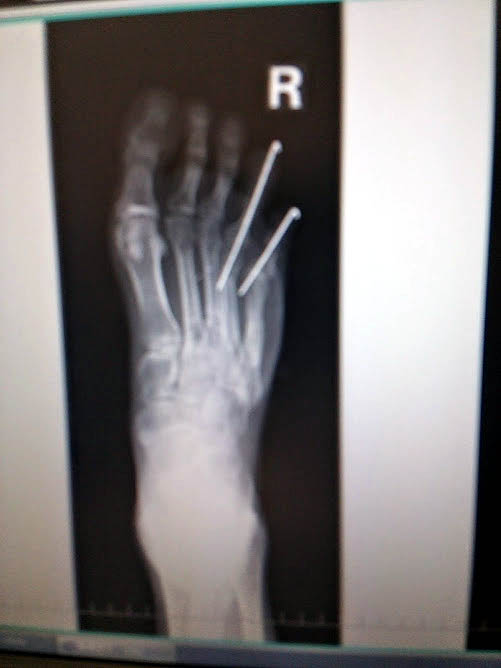

オペから1ヶ月経ちました

1ヶ月という目安はいろいろな起点

24日入院していたので早く感じます

指に刺さっているピンを抜きます

今回は

補助的なもので

細くて短めだけど

先生が力任せにゴイゴイと引っ張る

痛くはないがその力まかせが恐ろしい

またコレクションが増えました

ホチキスの位置に

本当は髄内釘とピンが来るはずだった

髄内釘は抜いてないけど

O病院はピンすらくれなかった

ただし今回はとうとう

足のラインが

変わってしまった

でもピンを抜いたせいで痛みが増し

時々鋭い痛みに襲われたり

右足全部が痛いからどうも動きが鈍い

今までは1ヶ月経てば元の生活に戻していけたけど

今回はスローな感じ